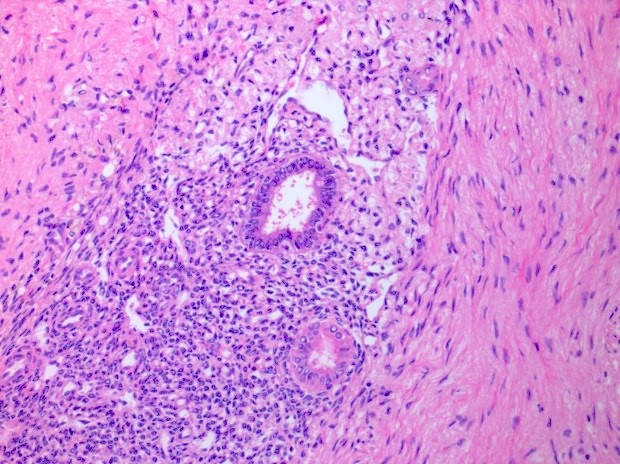

Microscopic (histologic) description

- At least 2 of the following 3 features

- Endometrial type glands

- Müllerian type epithelium (can be atrophic to cycling endometrium)

- Can show degenerative atypia (enlarged smudgy nuclei) or metaplasia

- Endometrial type stroma

- Often contains fine capillary network

- May undergo smooth muscle metaplasia, fibrosis (longstanding), decidual change

- Evidence of chronic hemorrhage (hemosiderin laden or foamy macrophages)

- Atypical endometriosis: this has been reported in 1.7 - 4.4% of endometriotic lesions and is considered the precursor lesion for endometriosis associated carcinomas (clear cell or endometrioid); may be in continuity with these tumors

- Includes crowded glands lined by atypical epithelium resembling endometrial atypical hyperplasia; nuclear atypia is typically moderate or severe, with hobnailing (Histopathology 1997;30:249, Case Rep Oncol 2013;6:480, Int J Gynecol Pathol 2023 Mar 13 [Epub ahead of print])

Microscopic (histologic) images